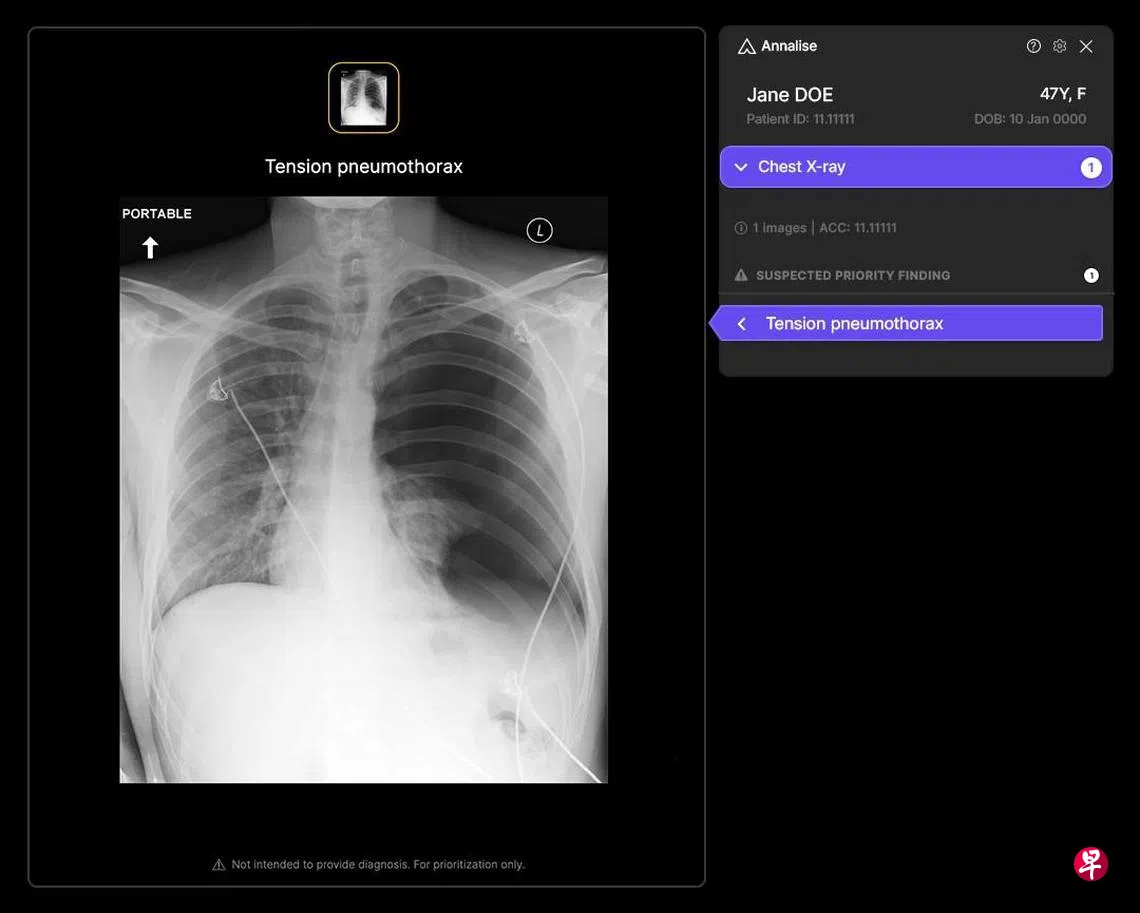

名为“Annalise Enterprise CXR”的系统,能在数秒内识别出胸腔X光片中多达124种影像征象。它可协助放射科医生更迅速地发现关键病症,包括早期或细微的病变,显著提升诊断能力和病患护理质量。

百汇放射科(Parkway Radiology)星期四(6月19日)宣布,和澳大利亚人工智能临床辅助方案业者Annalise.ai合作,首次在百汇旗下医院和诊所大规模采纳人工智能放射技术。